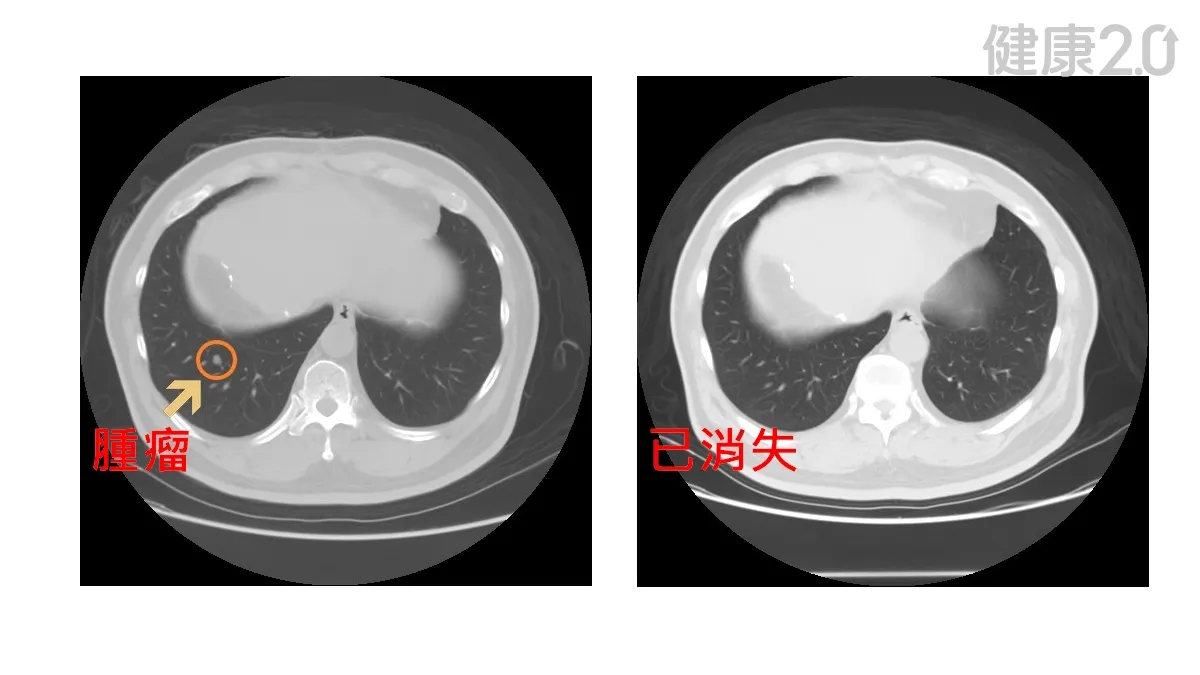

目前癌症治療的主流方向是提升免疫功能,找出致癌基因,促使癌細胞消滅。而在細胞治療方面,李思錦指出,台灣有多家醫學中心發展合法的細胞療法,但都屬於自費的研究性治療,尚未列入正規癌症治療指引。

這類療法通常是在其他治療效果不佳時,作為嘗試性的選擇。由於台灣法規限制和治療效果不明顯,加上費用高昂,許多病患選擇到醫療價格較低的國家尋求細胞療法。

李思錦提醒,對於三陰性乳癌這類難治型癌症,如果傳統治療無效,癌症持續生長,病患在經濟許可的情況下,確實是可以考慮嘗試細胞療法,但要先考慮好,一來這些治療的療效仍無法肯定,二來治療費用高昂,建議還是選擇合法的醫療單位提供的免疫細胞療法。